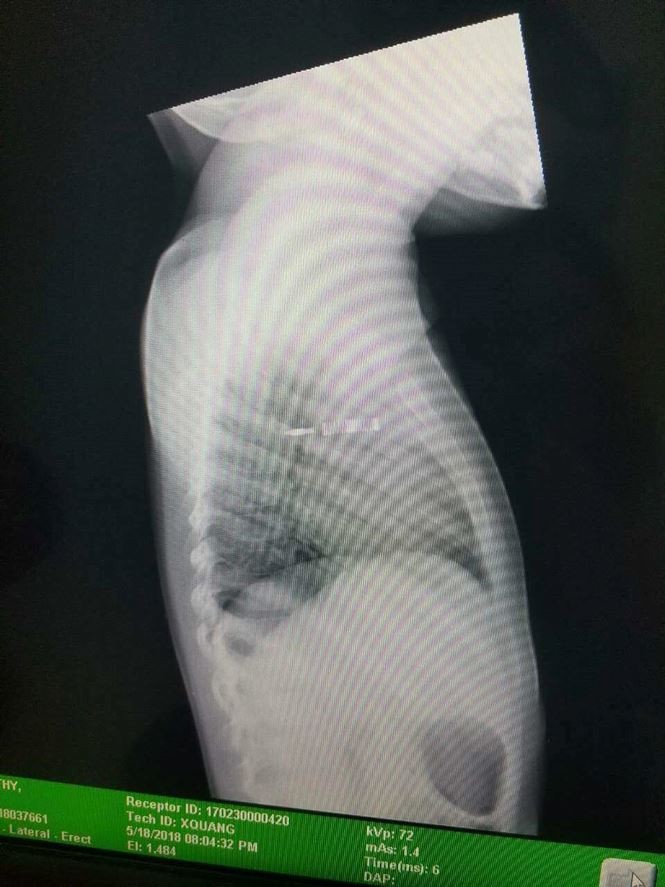

Ngay sau khi tiếp nhận bé gái, các BS tại BV Nhi đồng TP đã cho bênh nhi chụp X-Quang, kết quả cho thấy cây bút đâm gần lút cán khiến bé rách màng phổi, mũi bút nằm ngay giữa trung thất ở trung tâm lồng ngực, vừa xuyên thủng tĩnh mạch chủ trên nhưng may mắn chưa gây vỡ tĩnh mạch chủ. Bệnh nhi được tiến hành mổ cấp cứu, lấy cây bút ra khỏi ngực.